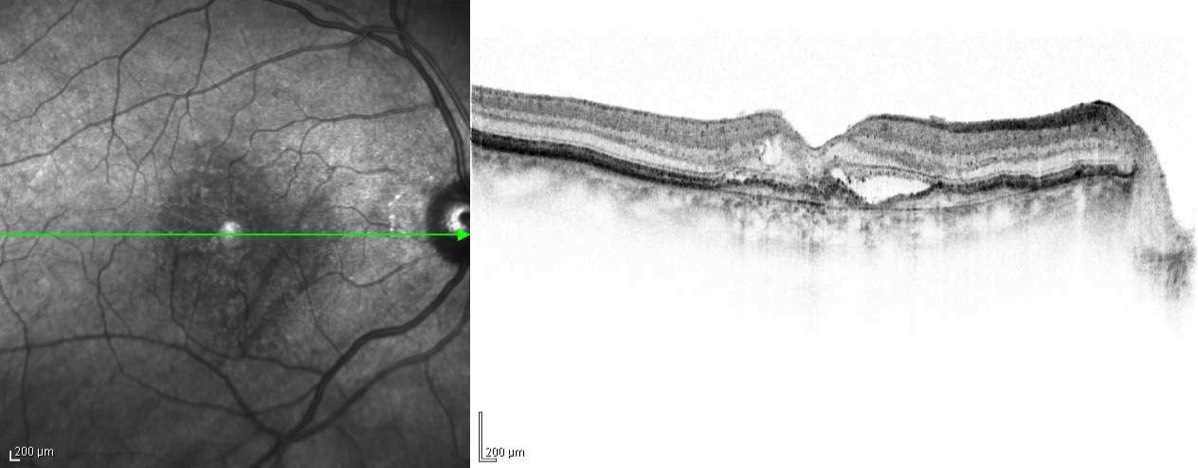

Stacks Image 606305

OCT-Bild: feuchte Makuladegeneration. Es sind intraretinale Zysten erkennbar, Zeichen für neovaskuläre Aktivität.